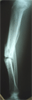

Mr. Jimmy, 19, Chinese,Male, presented with a painful deformed left Tibia

Pre

Op

▪ Left Tibia painful deformity and

shortening

▪ Walk with a limp

▪ Sinus